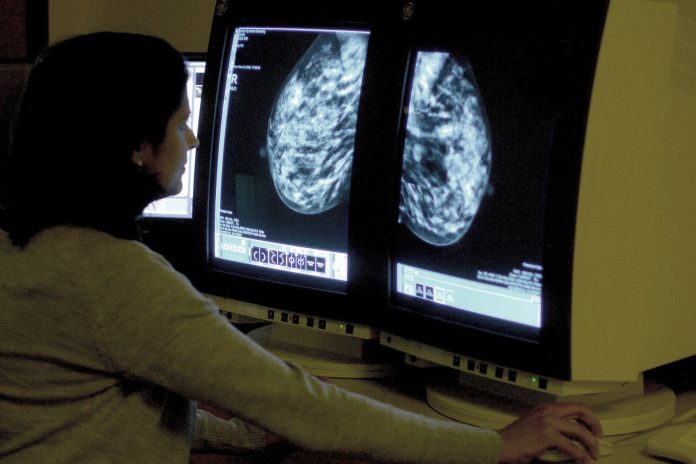

NEW DELHI, Sept 17: Researchers have developed an artificial intelligence tool that could predict the risk of heart disease in women by analysing their mammogram and age, without depending on an extensive medical history.

Described in a paper in the journal ‘Heart’, the AI tool was trained and validated using routine mammograms from over 49,000 women in the state of Victoria, Australia, obtained from hospital and death records.

“A deep learning algorithm based on only mammographic features and age predicted cardiovascular risk with performance comparable to traditional cardiovascular risk equations,” the authors wrote.

Arnott said, “Our model is the first to use a range of features from mammographic images combined simply with age — a key advantage of this approach being that it doesn’t require additional history taking or medical record data, making it less resource intensive to implement, but still highly accurate.”